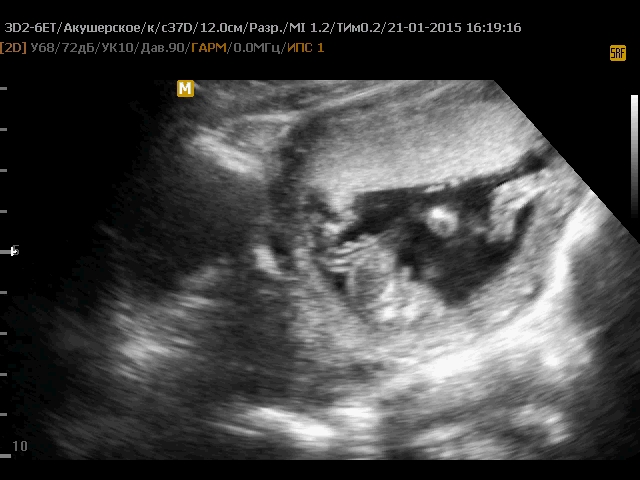

Узи 14 недель сказали девочка!!! Так что это между ножек у моей девочки?

Вчера делала узи, 14 неделя, врач сказала, что точно доченька, насчитала 4 половых губки. По показаниям узи, ребенок опережает на неделю. Так что я счастлива, девочка...

Мне в 3д сложно понять... У меня она прям с раздвинутыми ножками была, что было видно две по две, а между разрез. Но она опережает размеры, по всем показателям от 14 с половиной до 15. Может из-за этого у вас непонятно...

А на этом фото девочка или мальчик? )) мне не понятно. Сегодня точно так же мне показали. между ног две полосочки как будто. Вроде девочка, но при другом наклоне на мальчика похоже потому что сильно торчат они

У всех малышей на этом сроке между ножек отросточек:) Половые наружные органы начинают формироваться в 16-20 недель:) Пол ребенка в 14 недель определяют по углу наклона отросточка этого:) Так что...

Значит у нас есть шанс ещё на мальчика. Этот кадр я заметила после просмотра видео в 20й раз, я уверена что врач даже не заметил этот кадр, так как в основном только разговаривал, а процесс определения пола в 14 недель длился максимум 2 минуты. С видео в 12 недель просмьтря его  тоже раз 30 я увидела половой бугорок направленный чётко вверх под 90 градусов. ,